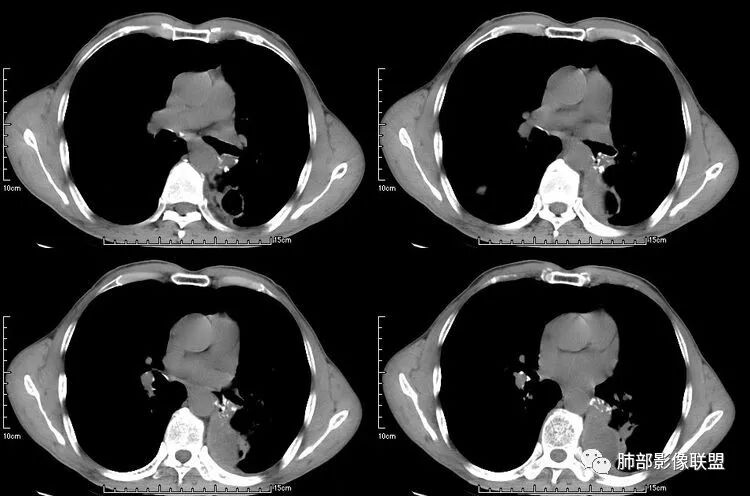

无发热,其他慢性细菌先不考虑,有的低毒的,但是结节形态还是比较不规则的,分布也是比较随机,更像原发病灶。真菌方面,结节没有融合,坏死也是液化坏死,不符合隐球菌,曲霉不符合IPA,慢性吸入的也少见。结核没有树丫,不考虑。鉴别主要是GPA,和肺癌。GPA不支持点是皮肤,肾脏没有累及,ANCA不支持。。。肺癌主要是腺癌和鳞癌转移。比较支持的是淋巴结肿大,和左下肺的主病灶,支气管堵塞和异常强化。还有分叶,局部膨隆。可以建议支气管镜检测。

本病例左肺下叶肿块,有深分叶、毛刺、胸膜牵拉凹陷、支气管截断及纵隔内淋巴结肿大等征象,都均支持病灶为恶性,如腺癌,而且叶间裂的多发结节也提示是腺癌来源可能大;双肺多发结节、肿块,大部分病灶有分叶、毛刺及胸膜凹陷的恶性征象,与原发肿瘤本身的性质有关,所以应该与左肺下叶肿块同源,而且双肺多发病灶内空洞也具有多样性;

此病例中空洞形态多样,内壁不光整,有分隔影,周围未见明显卫星灶及钙化灶,结核不太符合;患者病史慢性病史,无明显发热,缺乏中毒临床表现,急性感染基本排除;各种中性粒细胞胞浆抗体阴性,没有鼻窦炎,肾脏等病史,基本排除血管炎;霉菌性空洞常见于免疫机能低下者, 常为空洞、肺炎、伴“ 晕圈”征的结节及支气管扩张合并存在。